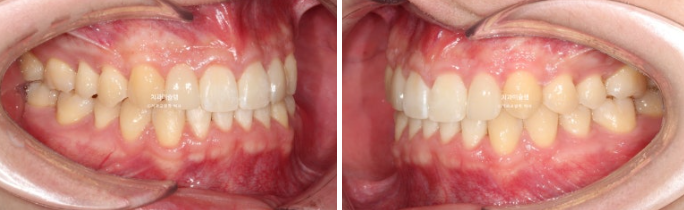

어금니 교합은 좋고 1급 교합관계를 보입니다.

전 후 볼게요

약간의 앞니뻗침 즉 돌출이 개선되었습니다.

한쪽의 가위교합을 해결함으로써 좌우 교합 밸런스가 좋아졌으니, 좌우 50대 50으로 씹는 연습을 하다보면 근육 비대칭으로 인해 한쪽 얼굴이 커보이는 부분도 차차 개선될 것입니다.